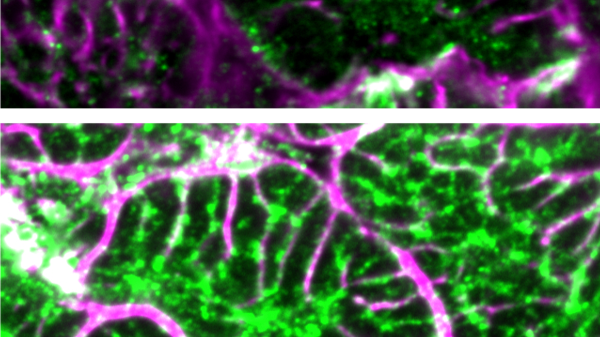

In the study, pigs with heart failure were found to have low levels of cardiac bridging integrator 1 (cBIN1), a critical heart protein.

The scientists injected a harmless virus into the pigs’ bloodstreams to carry the cBIN1 gene into their heart cells, according to a university press release.